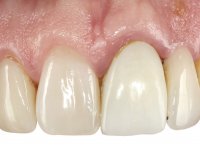

Arcade prints were made with irreversible hydrocolloid, for the lab to prepare an acrylic provisional bridge, with tooth 2.1 as abutment and tooth 2.2 as cantilever pontic. A palatal support was made to be bonded with the palatal surface of tooth 2.3. After removal of the Maryland bridge and the vestibular veneer from tooth 2.1, the dental abutment was re-prepared by making the cervical finish line intrasulcular. The provisional bridge made in the lab was relined on the mouth with self-curing acrylic and composite resin. During 6 weeks the soft tissues were worked and stabilized, preparing the consultation for impression. In this session, gingival separation was performed with kaolin paste, using the provisional bridge to compress the material into the gingival sulcus. Impression was performed using wash technique, and the provisional bridge was placed. At the end of the consultation, an impression was made from the provisional bridge placed in the mouth, using irreversible hydrocolloid. The patient had approved the aesthetics of the provisional. This information was passed on to the lab, where the work followed a silicone index, based on the shape and arrangement of the provisional bridge, approved by the patient. The cantilever bridge was built with a Zr infrastructure, with particular care in designing the connector. After being tried and approved by the patient, the prosthetic was cemented in the mouth with resin modified glass ionomer.